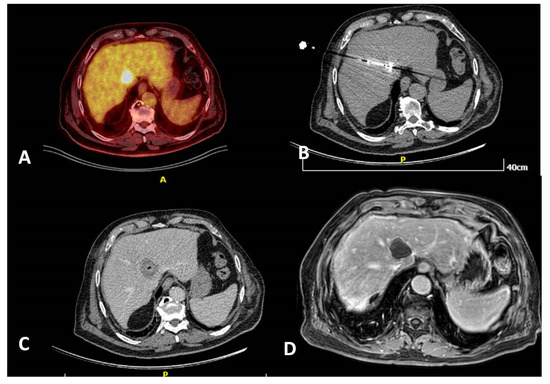

- Cornelis, F.; Sotirchos, V.; Violari, E.; Sofocleous, C.T.; Schoder, H.; Durack, J.C.; Siegelbaum, R.H.; Maybody, M.; Humm, J.; Solomon, S.B. 18F-FDG PET/CT is an immediate imaging biomarker of treatment success after liver metastasis ablation. J. Nucl. Med. 2016, 57, 1052–1057. [Google Scholar] [CrossRef]

- Mauri, G.; Gennaro, N.; De Beni, S.; Ierace, T.; Goldberg, S.N.; Rodari, M.; Solbiati, L.A. Real-time US-(18)FDG-PET/CT image fusion for guidance of thermal ablation of (18)FDG-PET-positive liver metastases: The added value of contrast enhancement. Cardiovasc. Intervent. Radiol. 2019, 42, 60–68. [Google Scholar] [CrossRef]

- Ryan, E.R.; Sofocleous, C.T.; Schöder, H.; Carrasquillo, J.A.; Nehmeh, S.; Larson, S.M.; Thornton, R.; Siegelbaum, R.H.; Erinjeri, J.P.; Solomon, S.B. Split-dose technique for FDG PET/CT-guided percutaneous ablation: A method to facilitate lesion targeting and to provide immediate assessment of treatment effectiveness. Radiology 2013, 268, 288–295. [Google Scholar] [CrossRef]

- Cornelis, F.H.; Petre, E.N.; Vakiani, E.; Klimstra, D.; Durack, J.C.; Gonen, M.; Osborne, J.; Solomon, S.B.; Sofocleous, C.T. Immediate postablation 18F-FDG injection and corresponding SUV are surrogate biomarkers of local tumor progression after thermal ablation of colorectal carcinoma liver metastases. J. Nucl. Med. 2018, 59, 1360–1365. [Google Scholar] [CrossRef]